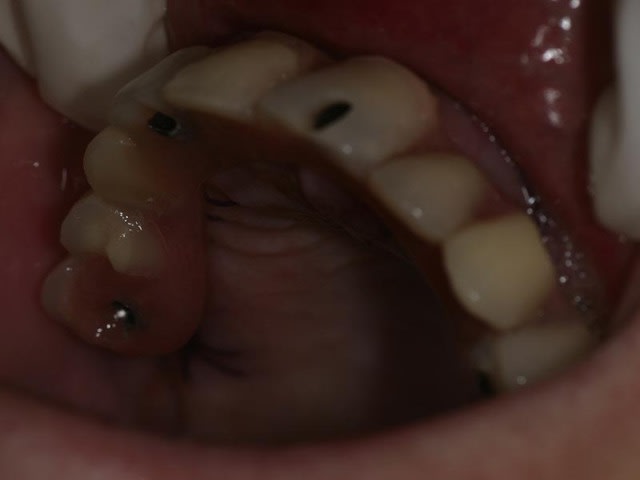

bon, toujours aussi speed je suis, mais après certaines réclamations, et malgrès ma réticence à poser un cas non "consolidé", voici en avant première mon premier all on 4, version photos ratées et non retouchées, mais... speed je suis je vous disais ;)

sto le bla bla, et pasons le diaporama... bon voyage au pays de la mise en charge immédiate totale au maxillaire de fille carole sur dame ginette, une patiente en or que j' adore, et pour qui je suis très très heureuse d' avoir pu réaliser cette chirurgie et la première étape prothétique.....